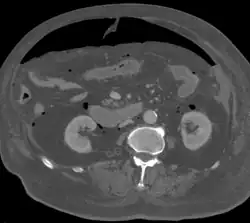

Objawem radiologicznym perforacji przewodu pokarmowego jest obecność wolnego gazu pod przeponą, który na zdjęciu jest widoczny jako przejaśnienie o kształcie sierpa lub rogala[10]. Powietrze zgromadzone pod kopułą przepony powoduje również zniesienie stłumienia wątrobowego podczas opukiwania jamy brzusznej[11]. W tomografii komputerowej widoczne jest wolne powietrze, wolny płyn poza światłem uszkodzonego narządu, nieciągłość ścian narządu, wyciek kontrastu lub obecność zmian zapalnych. TK pozwala dokładnie określić miejsce perforacji[12], jest szczególnie przydatna w diagnostyce "ukrytej perforacji" oraz "zamkniętej perforacji"[13]. Perforacja w obrębie klatki piersiowej (przełyk) w badaniu radiologicznym jest widoczna jako odma śródpiersiowa, odma podskórna, płyn w śródpiersiu oraz poszerzenie śródpiersia[9].